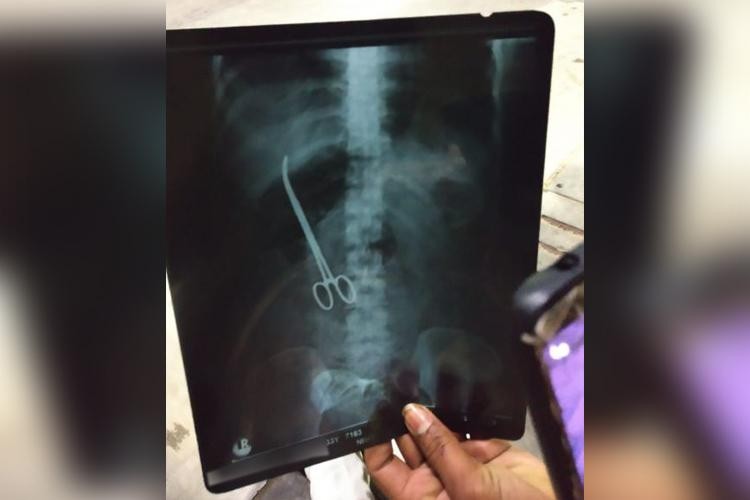

Hình ảnh chiếc kéo bị bác sĩ bỏ quên 3 tháng trong bụng bệnh nhân

Vụ việc hi hữu được đưa ra ánh sáng ngày 8/1 khi các bác sĩ của Bệnh viện Khoa học Y tế Nizam (NIMS) ở bang Telangana, Ấn Độ phát hiện một chiếc kéo phẫu thuật trong bụng một bệnh nhân nữ.

Trước đó, Maheshwari, 33 tuổi, đã trải qua một cơn đau bụng dữ dội. Ban đầu, người thân của cô nghĩ rằng nguyên nhân xuất phát từ cuộc phẫu thuật dạ dày của cô vào tháng 11 năm ngoái.

Tuy nhiên, cô gái và gia đình đã thực sự bị sốc khi kết quả chụp X-quang cho thấy chiếc kéo mà các bác sĩ tại NIMS đã bỏ quên trọng bụng cô sau ca phẫu thuật.

Bệnh viện này lúc đầu cố gắng che đậy vụ việc nhưng hôm thứ 7 đã chấp nhận thực hiện một cuộc phẫu thuật miễn phí để lấy chiếc kéo ra.

Giám đốc NIMS, tiến sĩ K Manohar, cho biết họ sẽ nhanh chóng điều tra về vụ việc.